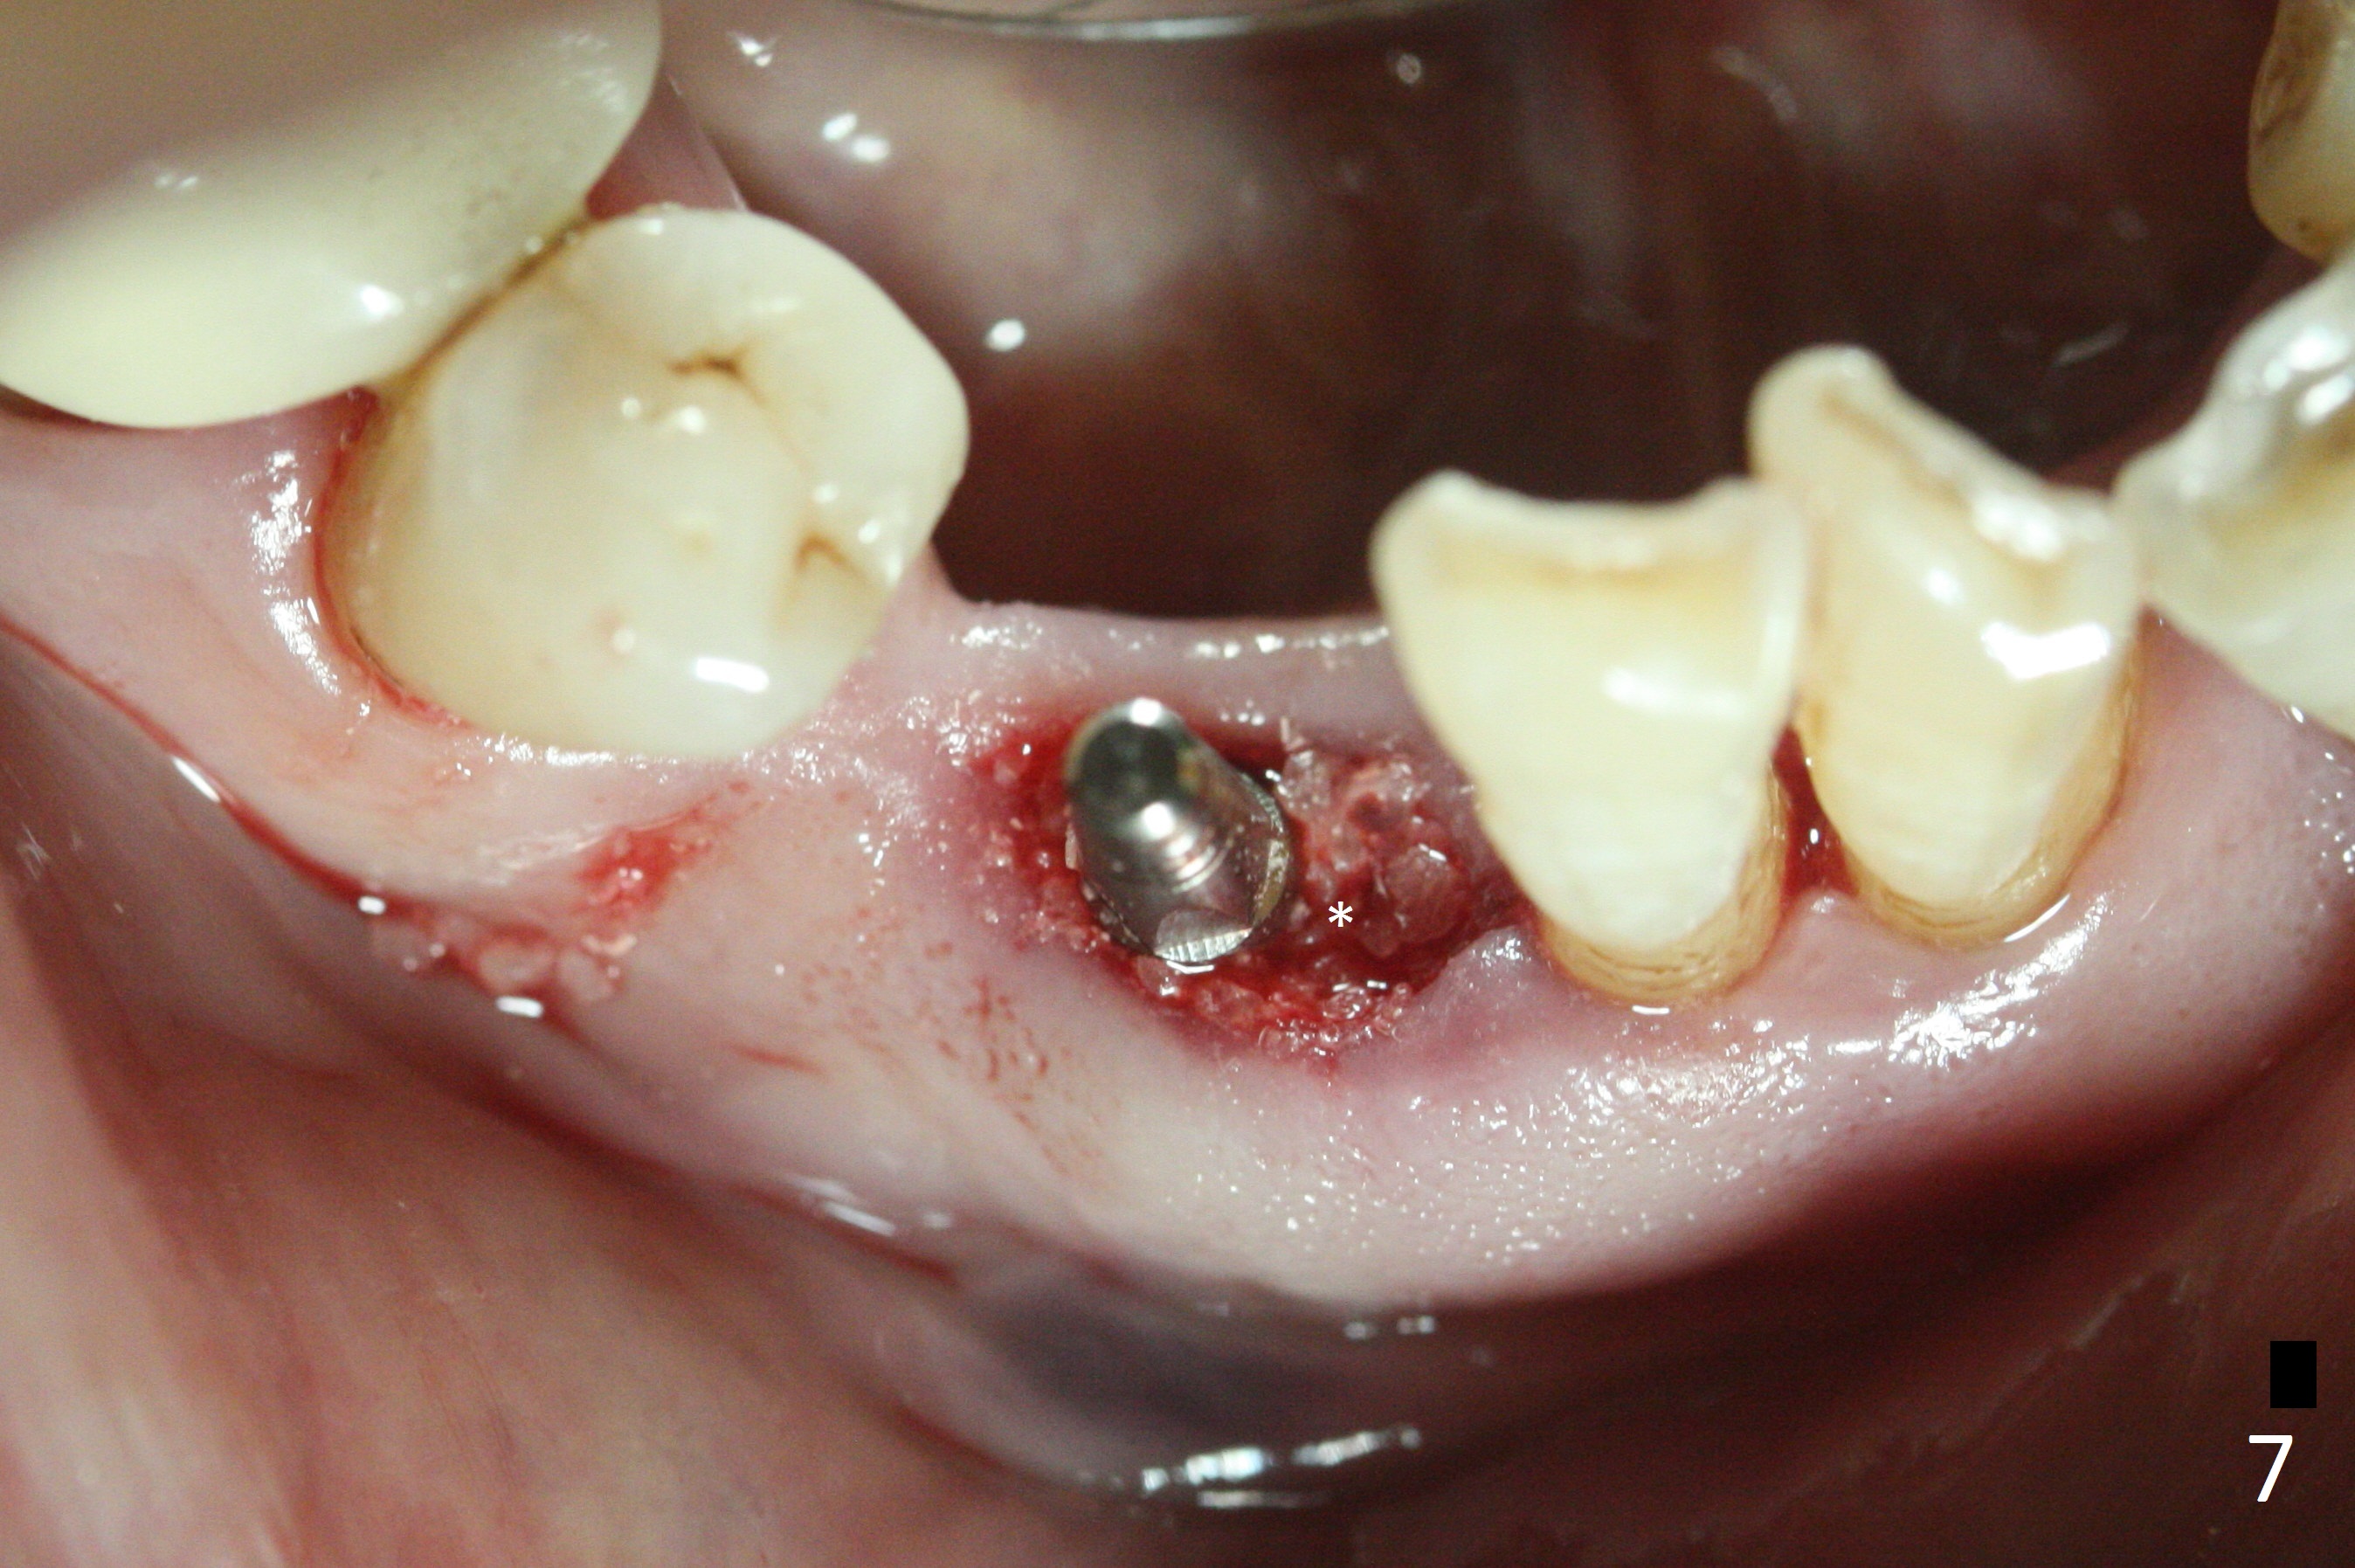

The lower dentition is special, consisting of a residual root (Fig.1 ^), 2 incisor (I), 1 canine (C), 1 premolar (P) and 1 molar (M). The residual root looks like an incisor with rotation of 90º (Fig.2,3). Osteotomy is initiated (Fig.4) for a 3x16(2) mm 1-piece implant (Fig.5 with 45 Ncm). The implant is being placed as distal as possible (Fig.4 arrow) so that a large canine-like provisional is to be fabricated in the large edentulous space (Fig.8,9) after bone graft (Fig.6,7 *). The gingiva around the provisional (Fig.10 P) remains healthy 11 days postop with occlusal clearance against the opposing dentition (Fig.11). The implant threads are not exposed with the help of bone graft 3 months 1 week postop (Fig.12). The gingiva around the implant is healthy (Fig.13). Soft tissue socket is formed by the provisional (Fig.14 *).